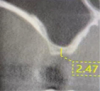

Three months later, a cone-beam computed tomography (CBCT) scan revealed the indication of a MSA due to a pneumatized right maxillary sinus with residual bone height of 2.5 mm and two Underwood septa (Figure 2). Prior to the MSA procedure, based on scientific protocols that suggest smoking cessation for at least 10 days before and after surgery,6,11 the patient was strongly advised to cease his smoking habits due to the risk of bone graft failure.

Fig 2. Preoperative CBCT scan showing a sagittal section of pneumatized right maxillary sinus in edentulous site No. 3.

Figure 2